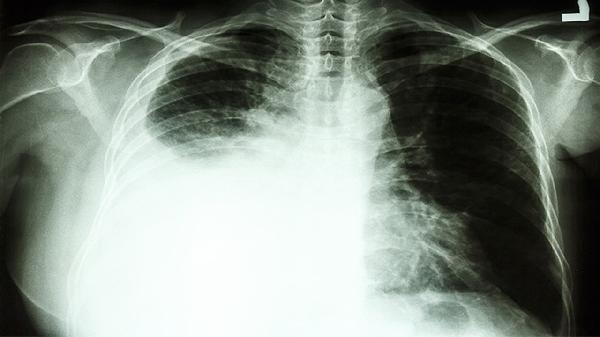

右肺门影增浓肺癌几率大吗

右肺门影增浓不一定是肺癌,可能与炎症、结核、淋巴结肿大等多种因素有关。影像学检查发现右肺门影增浓时,需结合临床表现、病史及其他辅助检查综合判断。

肺门区淋巴结肿大同样会导致影像学改变。长期吸烟、粉尘接触等刺激可能引发淋巴结反应性增生,矽肺等职业病患者更易出现。恶性肿瘤如淋巴瘤或转移癌也可表现为肺门影增浓,但多伴有进行性消瘦、咯血等警示症状。肺癌确实可能引起该表现,但通常需要观察到占位性病变、毛刺征等典型征象,确诊需依赖病理活检。